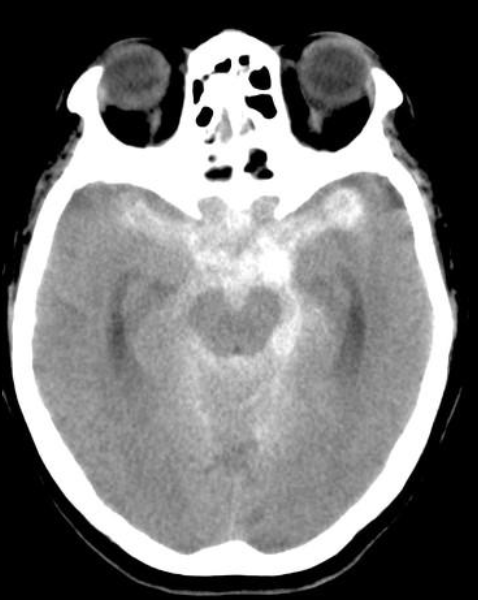

22

Q

A

EVC hemorragico

HSA